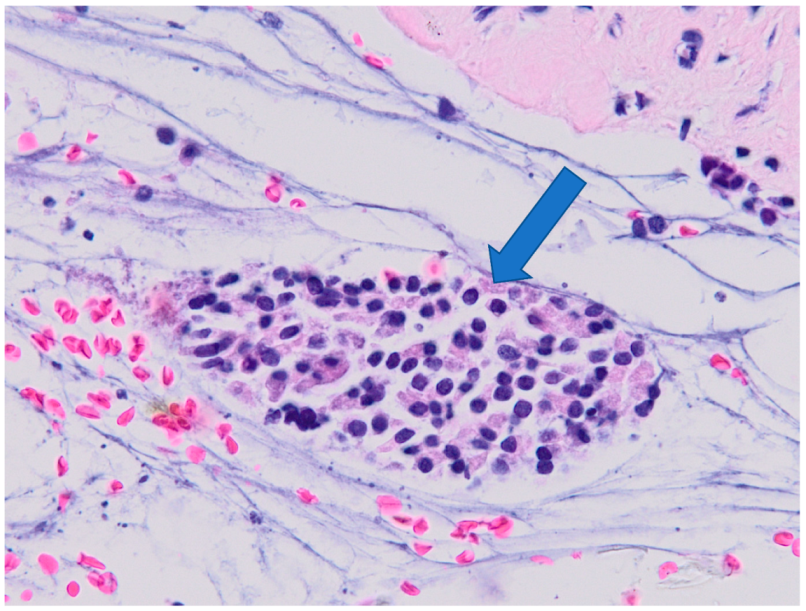

3.2. Histology

3.3. Correlation of Histology and Detected Compounds